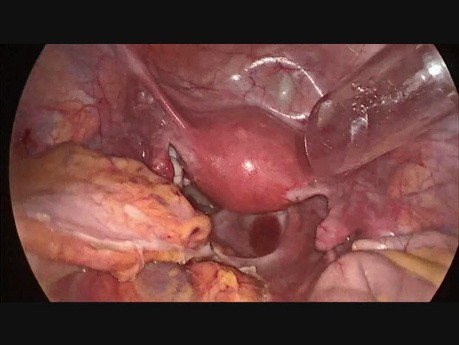

Laparoskpowa prawostronna hemikolektomia z usunięciem...

Film przedstawia przypadek prawostronnej hemiklektomii z użyciem trzech trokrów: 11,12,5 mm. Preparat usunięto przez pochwę oraz zastosowano nowe urządzenie pomagające chirurgowi w ekspozycji tkanek.